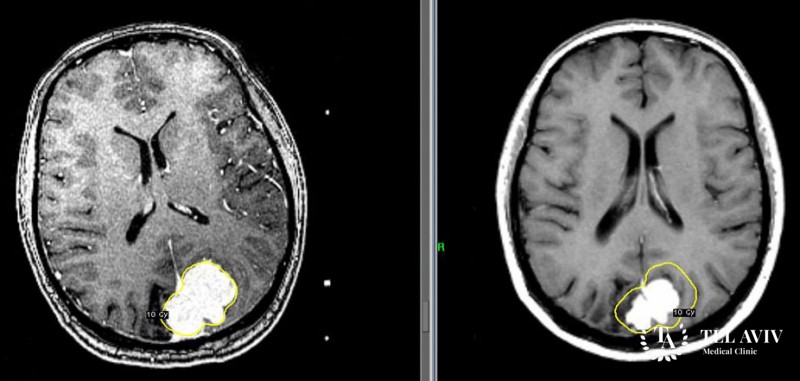

В израильском медицинском центре Tel Aviv Medical для диагностики менингиом используется ПЭТ-КТ и МРТ-диагностика с контрастом. В нашей клинике работают опытные врачи, для которых лечение менингиом является рядовой процедурой. Мы используем несколько методов лечения: лучевая терапия и хирургическое удаление менингиом. Также мы применяем роботизированную хирургию, что позволяет нашим специалистам полностью удалить опухоль без боли и риска повреждения важных структур мозга.